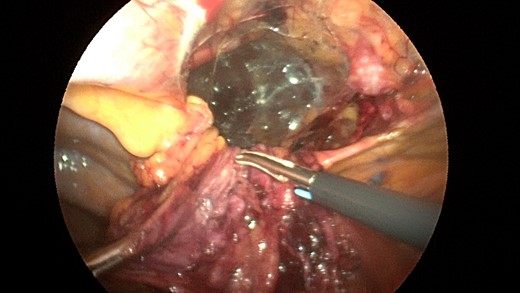

Patient underwent a laparoscopic approach in lithotomy positioning with the primary surgeon working between the legs. Three working ports were used, a 12 mm port at the umbilicus and two 5 mm ports; one in the LUQ and one in the RUQ. Upon initial laparoscopy multiple loops of small bowel were progressively reduced out of the hernia sac which also included the ascending colon and part of the transverse colon (Figs 3 and 4). All the small bowel and the colon appeared viable. The redundant parietal peritoneal hernia sac was excised out of the right inferior hemithorax utilizing a LigaSure (Covidien) (Fig. 5). The falciform ligament was also taken down all the way to the diaphragm. The defect in the diaphragm measured to be approximately 9 cm by 4 cm. A section of Pariatex composite mesh was then trimmed to 2 cm in width by 9 cm in length. Three stay sutures of 0 Ethibond were placed laterally and in the middle of the mesh. This was placed into the peritoneal cavity after soaking it in vancomycin with local anesthetic. The sutures were then percutaneously brought through the diaphragm edge that was unattached to the anterior abdominal wall and then subsequently through the anterior abdominal wall. These were then tied thereby re-approximating the unattached edge of the diaphragm to the anterior abdominal wall near the xiphoid (Fig. 6). Additional 0 Ethibond sutures were placed in between these initial ones percutaneously with a suture passer.

Laparoscopic view of the retroxyphoid defect in the diaphragm demonstrating multiple loops of small bowel and colon.

Closer view of the retroxyphoid defect demonstrating its large size with the edge of the diaphragm unattached to the undersurface of the abdominal wall.